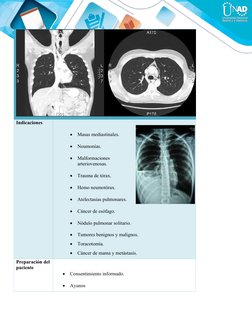

TAC DE TÓRAX CONTRASTADO

Indicaciones

 Masas mediastinales.

 Neumonías.

 Malformaciones

arteriovenosas.

 Trauma de tórax.

 Hemo neumotórax.

 Atelectasias pulmonares.

 Cáncer de esófago.

 Nódulo pulmonar solitario.

 Tumores benignos y malignos.

 Toracotomía.

 Cáncer de mama y metástasis.

Preparación del

paciente

 Consentimiento informado.

 Ayunos

Imágenes